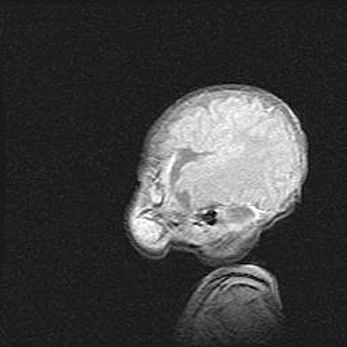

Мальформация Денди-Уокера. Киста задней черепной ямки.

Агенезия мозолистого тела.

Возраст: 2,5 месяца

Вес: 2420 г

Пол: женский

Окружность головы: 37 см

Срок гестации: 32 недели

Мальформация Денди—Уокера — редкий вид патологии ЦНС, представляющий собой врожденный порок развития каудального отдела ствола и червя мозжечка, ведущий к неполному раскрытию срединной (Мажанди) и латеральных (Лушка) апертур IV желудочка мозга. Для этогно синдрома характерна триада симптомов: гипотрофия червя мозжечка и/или полушарий мозжечка, кисты задней черепной ямки, гидроцефалия различной степени. В 70% случаев порок сочетается и с другими аномалиями головного мозга, в частности с агенезией мозолистого тела.